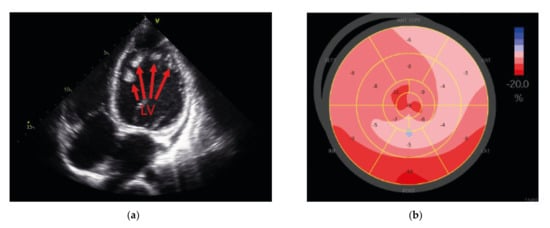

2.1. Compound Heterozygous FKTN-Genotype Presumably Led to Cardiomyopathy in a Young Patient

2.2. Neuromuscular Disease and Elevated CK Values in a Young Patient with Dilated Cardiomyopathy